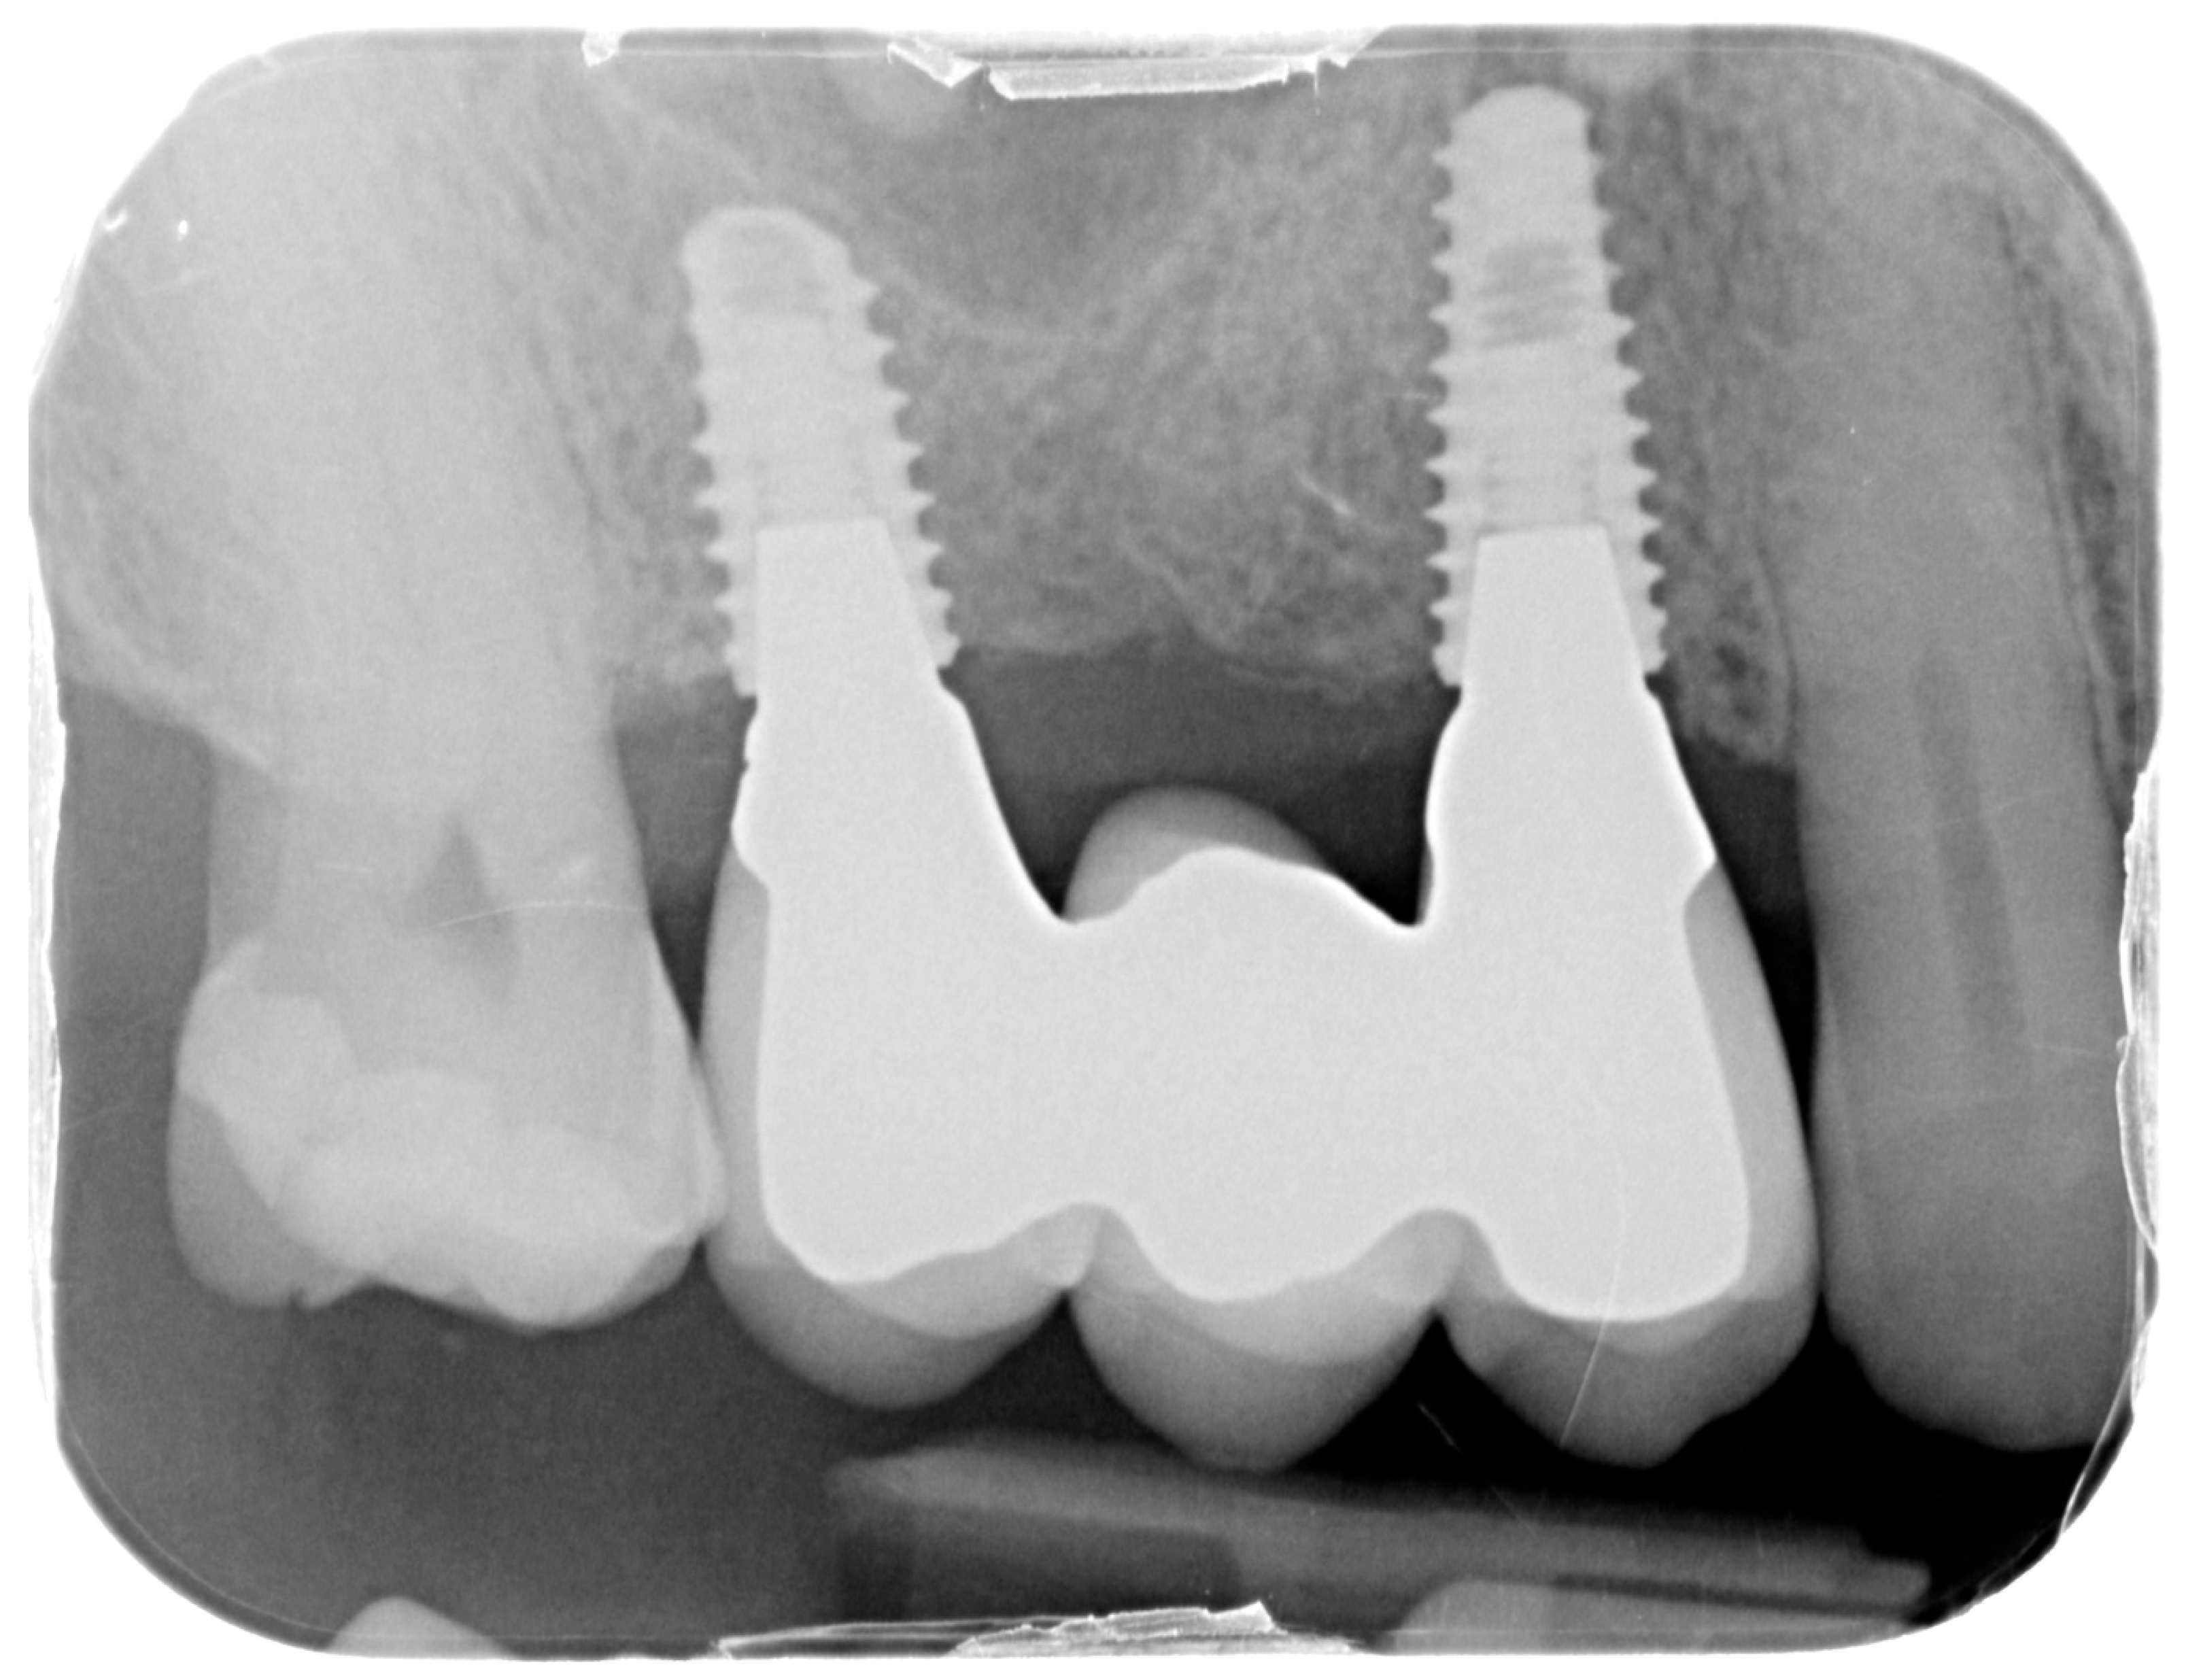

For the evaluation of the mesial and distal MBL, intraoral digital radiographs were taken using the long-cone paralleling technique with the central beam directed to the alveolar crest. Periapical radiographs were taken at the delivery of the prosthesis and after 1 year of prosthetic loading (T2). The mesial and distal MBL, i.e., the distance between the top of the implant shoulder and the first visible bone-to-implant contact, were measured at the mesial and distal aspect with a 10–15× magnification using an image analysis programme (ImageJ v 1.49, NIH, Bethesda, MA, USA). The length of the implant was used as known measure for the calibration and determination of the exact magnification and distortion of the images. All measurements were performed by two examiners to the nearest 0.1 mm. In case of disagreement, the evaluation was re-done and results discussed until an agreement was found.

Figure 13. Intraoral X-ray at one year follow-up.